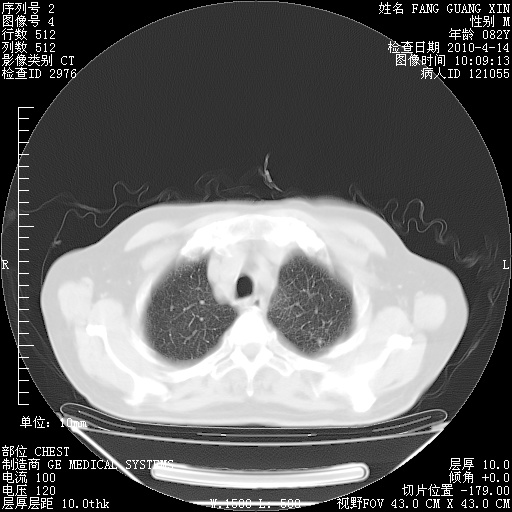

肺部CT平扫未见异常。